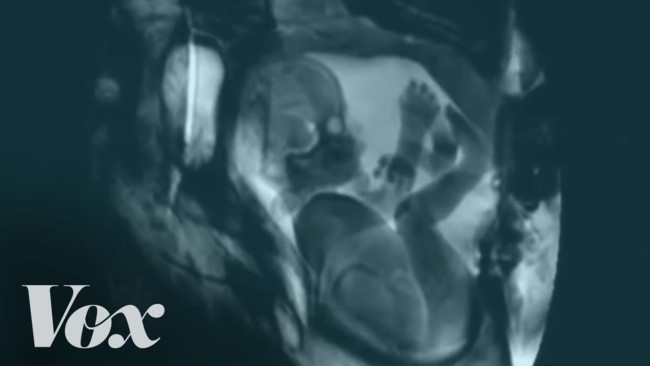

Otra de las posibles fuentes de información es la resonancia magnética, aunque no es un sistema muy cómodo y hasta que no evolucione un poco el tema no creo que se utilice mucho para estudiar los embarazos y partos. A pesar de ello, corre por internet este vídeo que nos muestra diferentes momentos de la vida diaria a través de una resonancia: el corazón latiendo, un alemán y un chino hablando, una pareja manteniendo relaciones sexuales, un bebé en la barriga de su madre, dos gemelos en la misma situación y un cuarto bebé naciendo, entre otras cosas.

Pero esos pocos segundos son suficientes para soltar algo así como un "Wow". Me ha hecho especialmente gracia la secuencia de los dos bebés gemelos en que uno de ellos vive ahí dentro como un rey y el otro, pobrecito, vive encorvado, sin espacio, y moviéndose por si entre patada y patada logra un centímetro cúbico más de espacio vital. Por suerte, he encontrado un vídeo un poco más extenso de ese momento, os lo dejo a continuación: